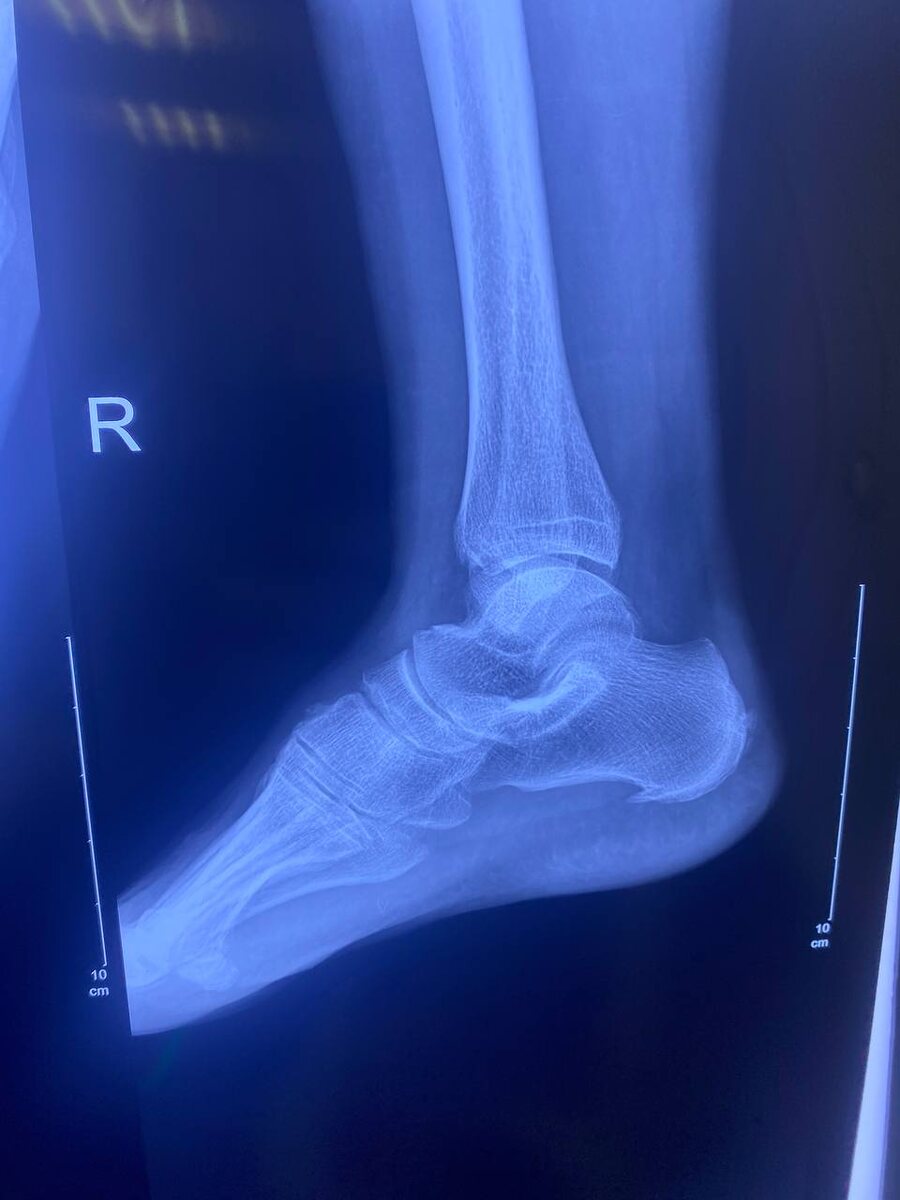

Пяточная шпора – это распространенное заболевание, возникающее в результате воспаления подошвенной фасции. Характеризуется образованием остеофита на пяточной кости, что вызывает сильную боль и дискомфорт при ходьбе. В этой статье мы обсудим симптомы пяточной шпоры, причины, по которым домашние методы лечения могут не помогать, и действительно эффективное решение – ударно-волновую терапию.

Симптомы пяточной шпоры

Основной симптом пяточной шпоры – это сильная и резкая боль в области пятки, которая может усиливаться при:

• Первых шагах после долгого отдыха (например, утром после сна или после длительного сидения).

• Длительной физической нагрузке.

• Хождении по ровной поверхности.

Боль может быть острой или тупой, и часто сопровождается ощущением жжения. Возможно также наличие отека и покраснения в области пятки.